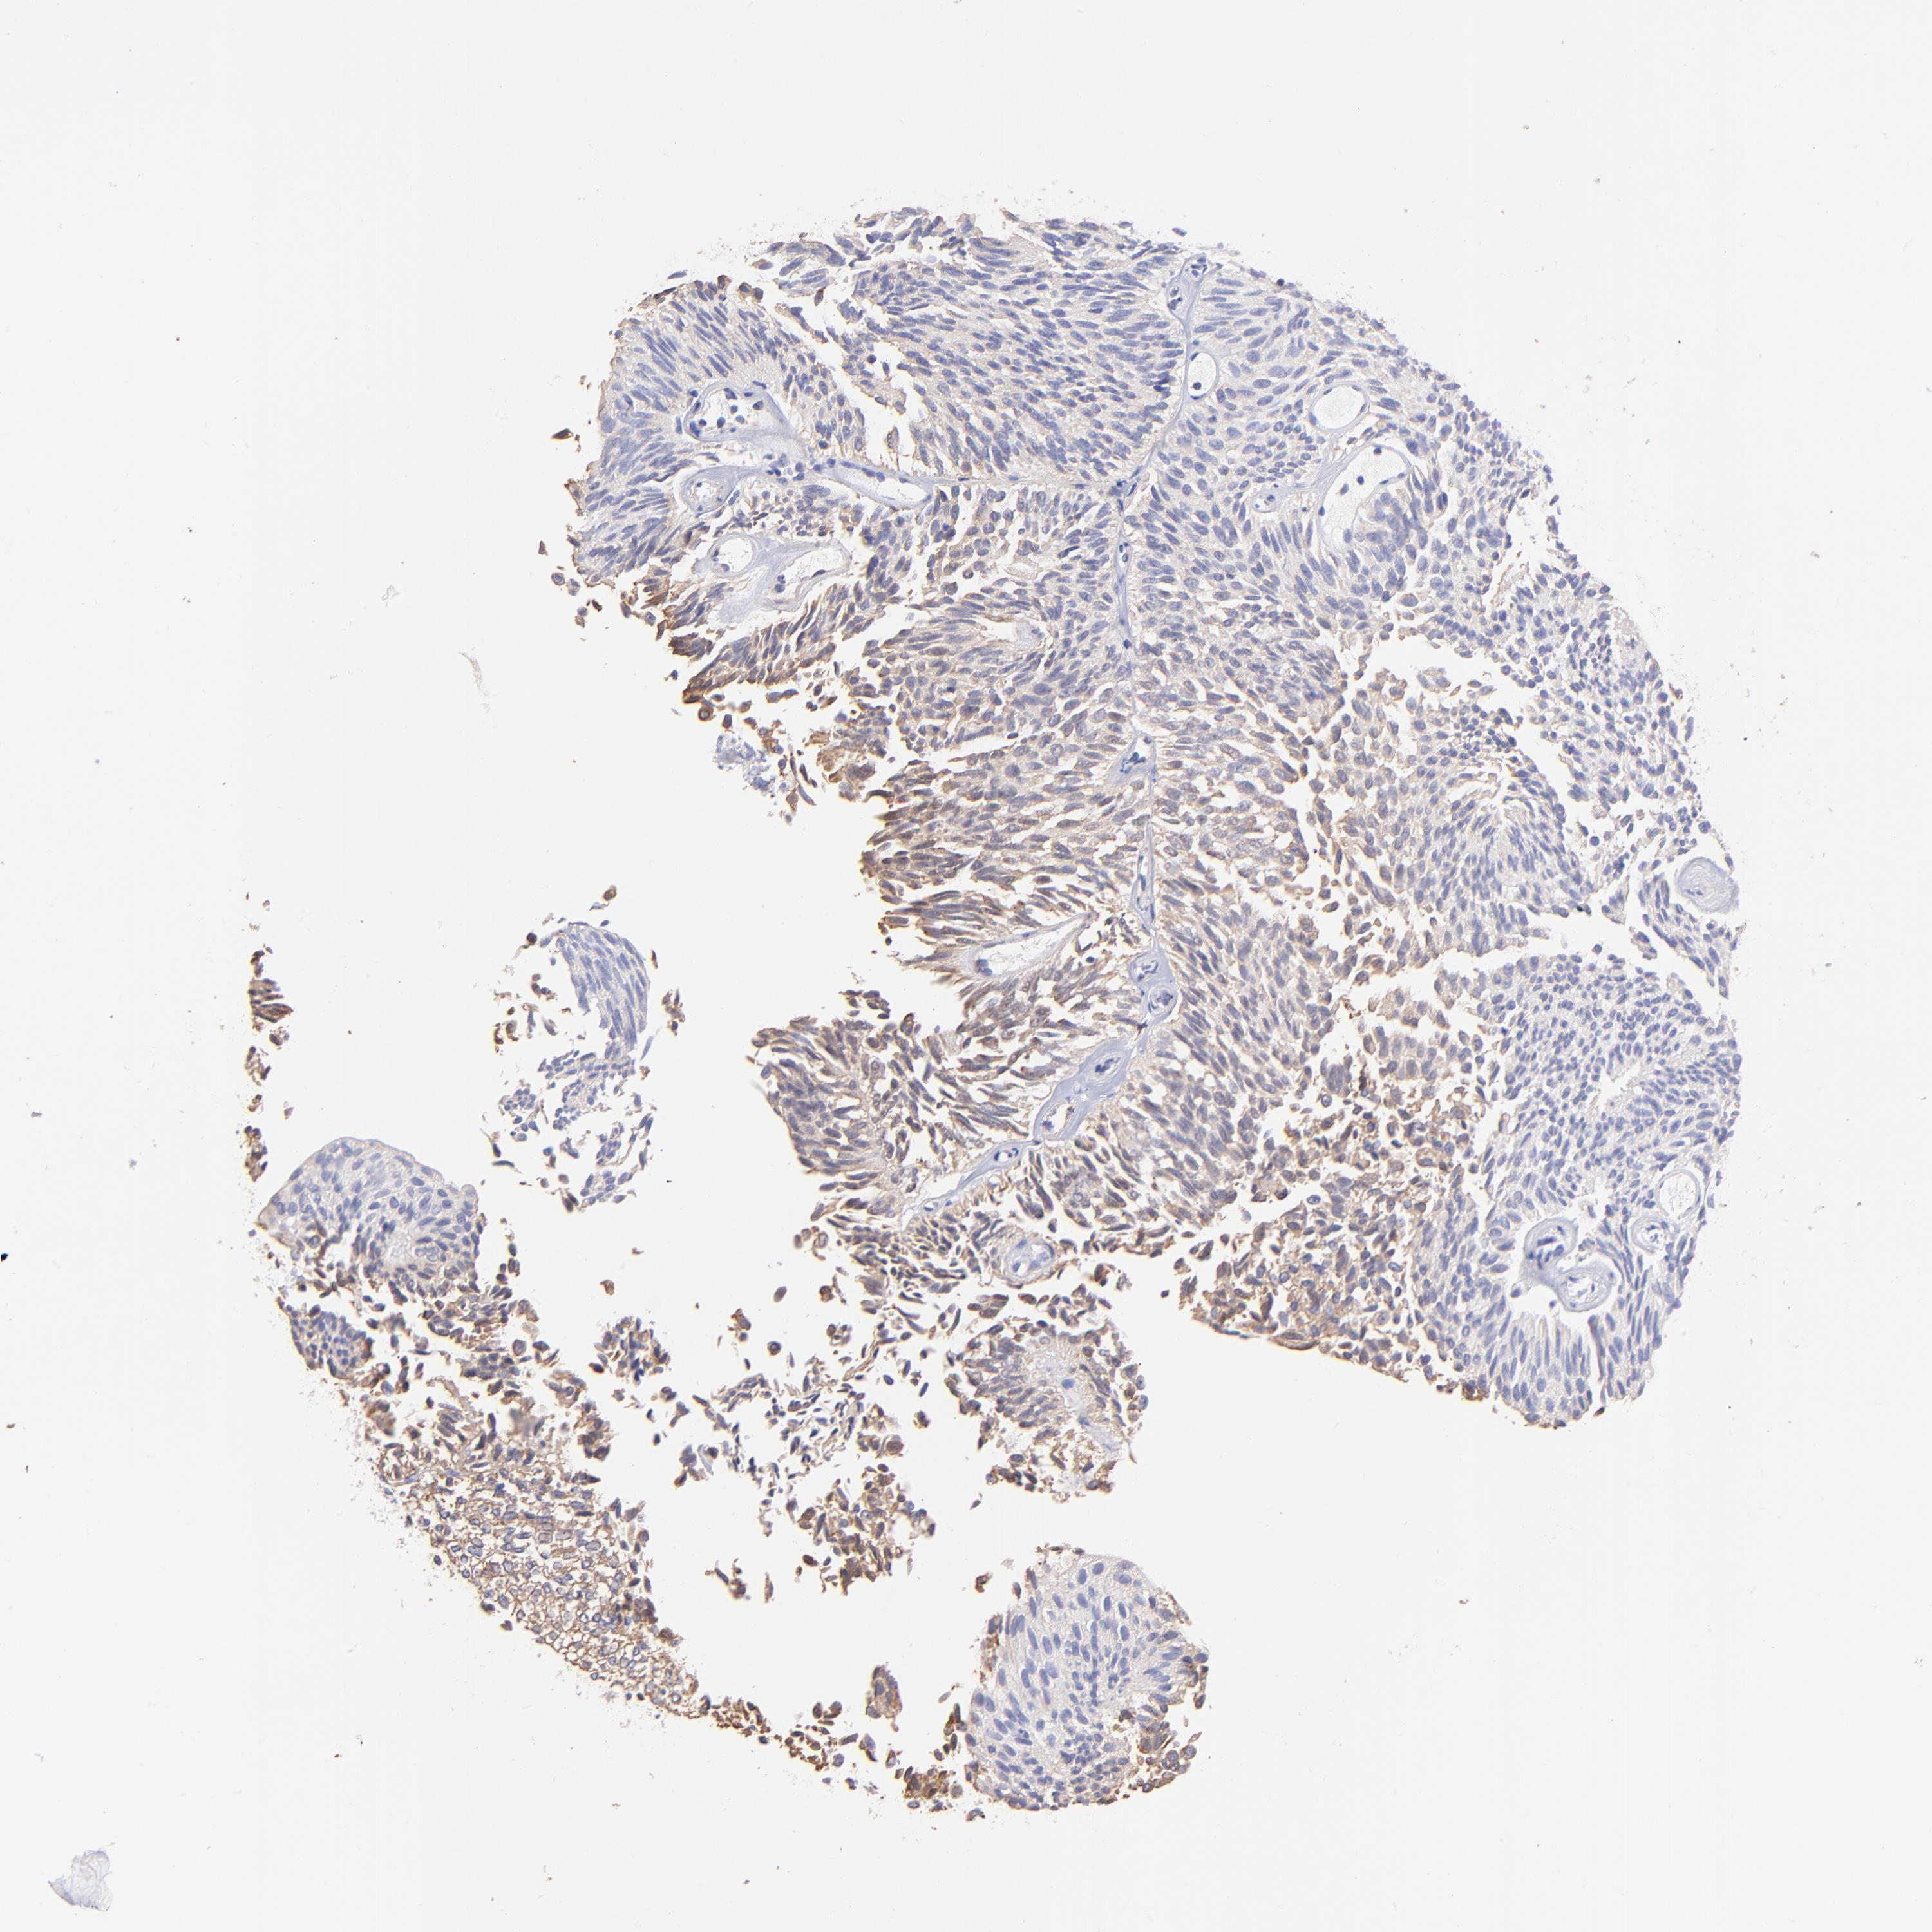

UROTHELIAL CANCER - Protein expressioni

A mouse-over function shows sample information and annotation data. Click on an image to view it in a full screen mode. Samples can be filtered based on level of antibody staining by selecting one or several of the following categories: high, medium, low and not detected. The assay and annotation is described here.

Note that samples used for immunohistochemistry by the Human Protein Atlas do not correspond to samples in the TCGA dataset.

Antibody stainingi

Antibody staining in the annotated cell types in the current human tissue is reported as not detected, low, medium, or high, based on conventional immunohistochemistry profiling in selected tissues. This score is based on the combination of the staining intensity and fraction of stained cells.

Each image is clickable and will lead to virtual microscopy that enables deeper exploration of all samples and also displays staining intensity scores, fraction scores and subcellular localization as well as patient and tissue information for each sample.

Antibody HPA002651

Staining

High

Medium

Low

Not detected

Intensity

Strong

Moderate

Weak

Negative

Quantity

>75%

75%-25%

<25%

None

Location

Nuclear

Cytoplasmic/membranous

Cytoplasmic/membranous,nuclear

Urothelial carcinoma, High grade

Urothelial carcinoma, Low grade